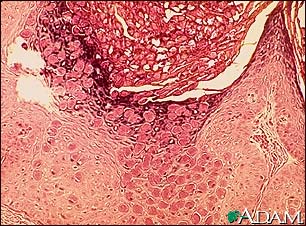

Molluscum, microscopic appearance

This is how a molluscum lesion appears under microscopic examination. Molluscum are small, raised, pearly skin lesions caused by the molluscum virus, a member of the poxvirus family.